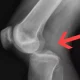

- پارگی رباط ها: زانو چهار رباط اصلی دارد که وظیفه پایداری آن را بر عهده دارند. آسیب یا پارگی هر یک از این رباط ها، به خصوص رباط صلیبی قدامی (ACL)، می تواند باعث احساس ناپایداری و خالی کردن زانو شود. برای اطلاعات بیشتر مطلب پارگی رباط صلیبی را بخوانید.

- ناپایداری کشکک زانو: اگر استخوان کشکک از محل اصلی خود در شیار استخوان ران خارج شود، فرد احساس خالی کردن زانو را تجربه خواهد کرد. این اتفاق ممکن است به دلیل ضربه مستقیم یا پیچ خوردگی ناگهانی زانو رخ دهد.